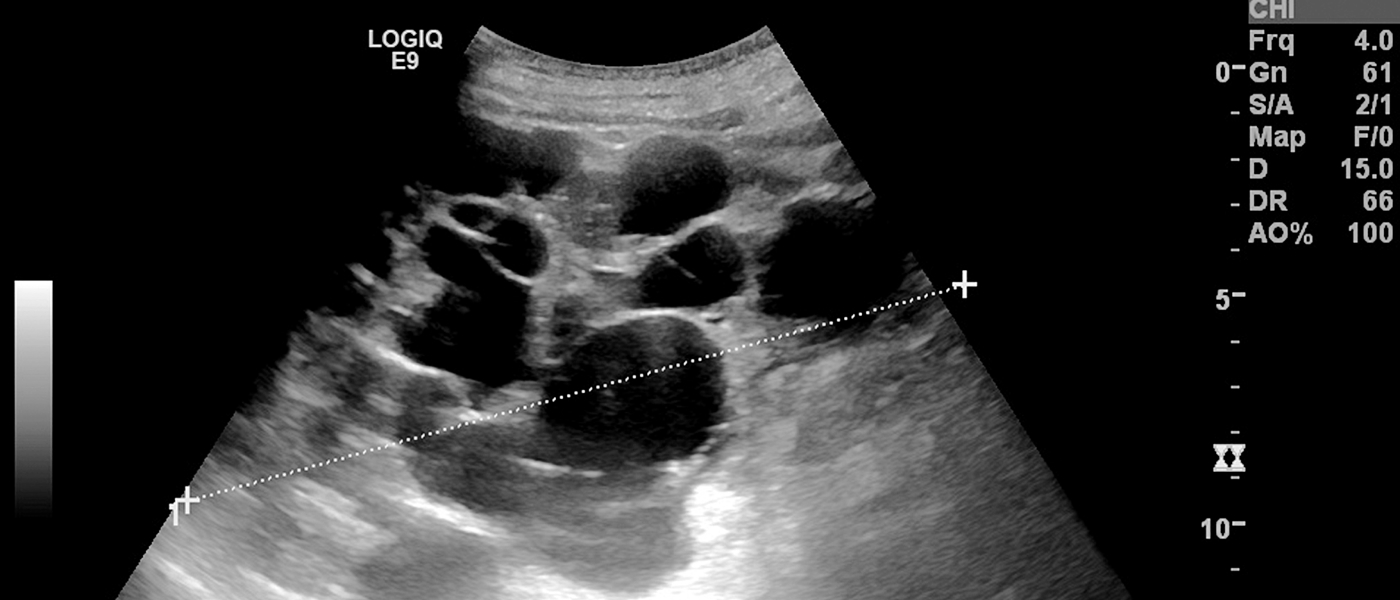

신우신염(신장 감염), 신장결석, 만성신부전, 신낭종 등이 주요 질환입니다.